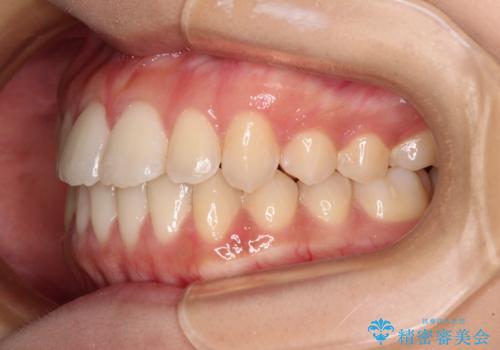

- 上下のデコボコと奥歯の咬みにくさを気にして来院された患者様です。

上顎骨の幅が下顎骨よりも小さく受け口傾向であったため、拡大装置により上顎骨の骨幅を広げて上下関係を改善し、その後インビザラインにて歯並びを整えることとしました。

下顎歯列は上顎歯列内に収まるように並んでいますが、上顎骨の幅が狭いと、下顎臼歯が全体的に舌側に傾斜した歯列となってしまいます。

舌側に傾斜した歯列は奥歯に力の負担がかかりやすく、歯磨きがしにくいなどの問題があるため、上顎骨拡大により舌側傾斜を改善することが可能となります。